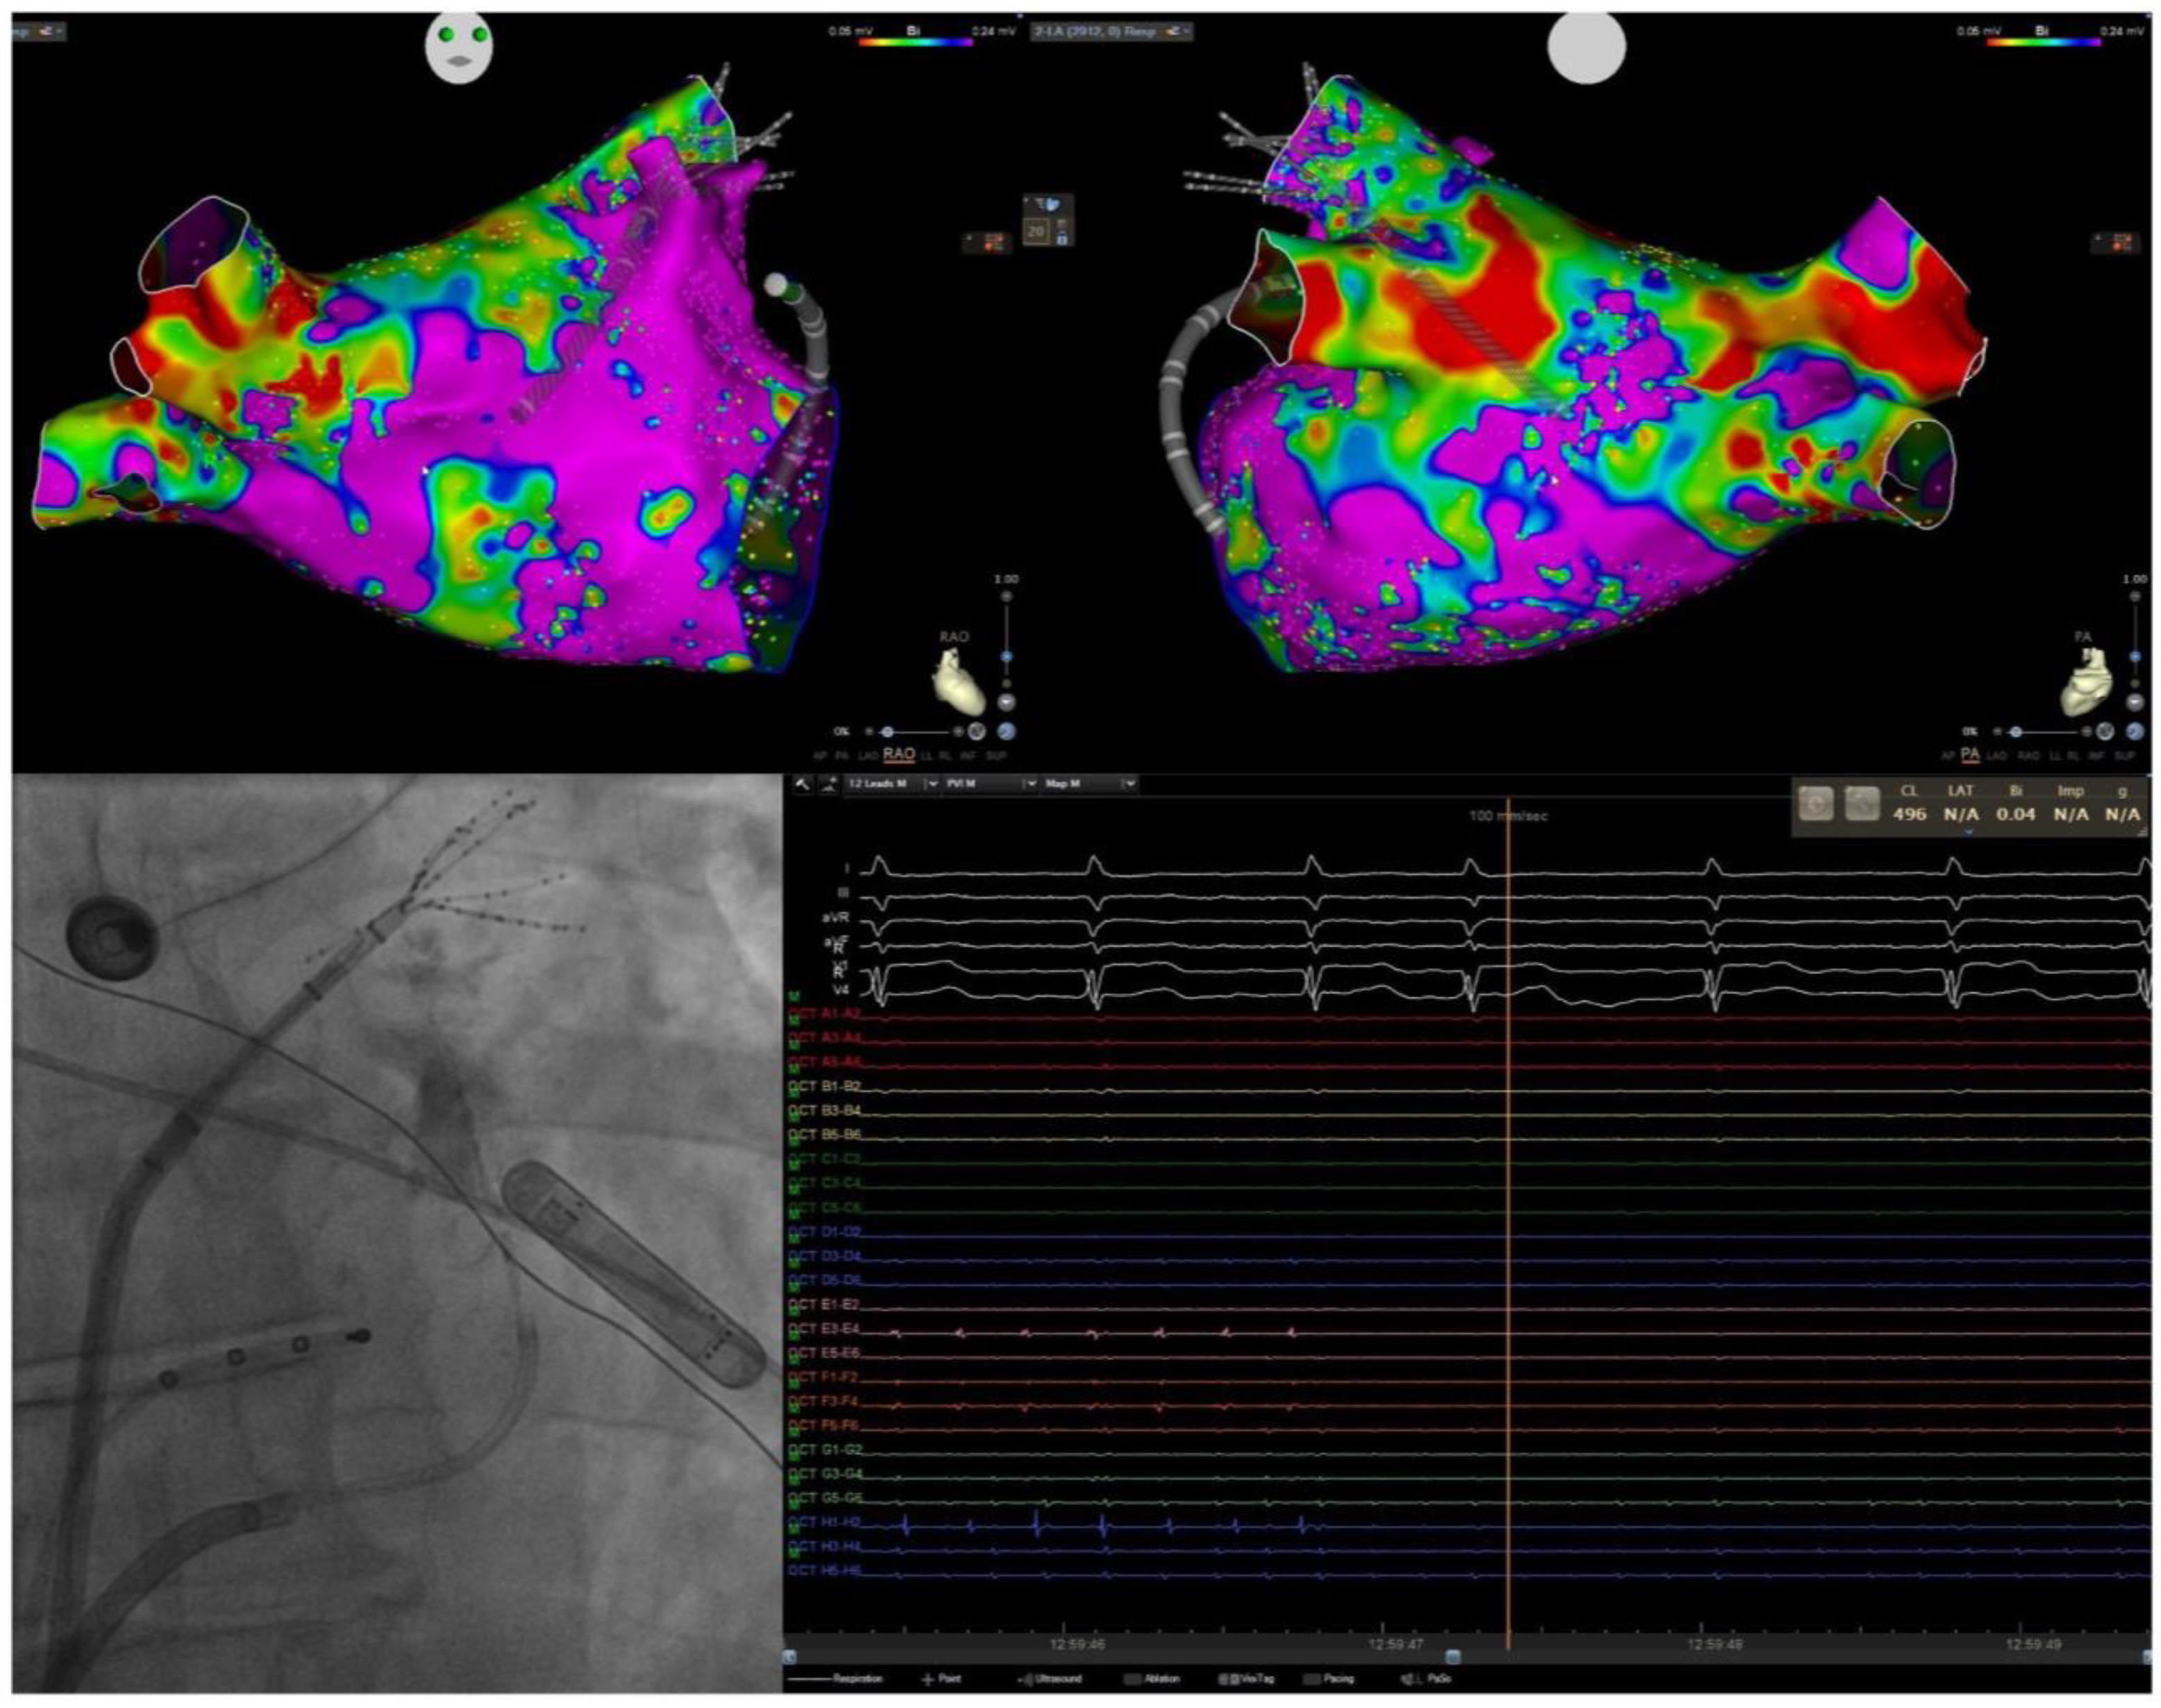

- DeLurgio, D.B.; Crossen, K.J.; Gill, J.; Blauth, C.; Oza, S.R.; Magnano, A.R.; Mostovych, M.A.; Halkos, M.E.; Tschopp, D.R.; Kerendi, F.; et al. Hybrid Convergent Procedure for the Treatment of Persistent and Long-Standing Persistent Atrial Fibrillation. Circ. Arrhythmia Electrophysiol. 2020, 13, e009288. [Google Scholar] [CrossRef]

- Bianchini, L.; Schiavone, M.; Vettor, G.; Gasperetti, A.; Penza, E.; Ballotta, A.; Pirola, S.; Brambillasca, C.; Zito, E.; De Lio, F.; et al. Hybrid-Convergent Procedure or Pulsed Field Ablation in Long-Standing Persistent Atrial Fibrillation. JACC Clin. Electrophysiol. 2024, 10, 1700–1710. [Google Scholar] [CrossRef]

5.3. Empirical Anatomical “Compartmentalization” (Cox-Maze-like Strategy) and Role of Epicardial Connections